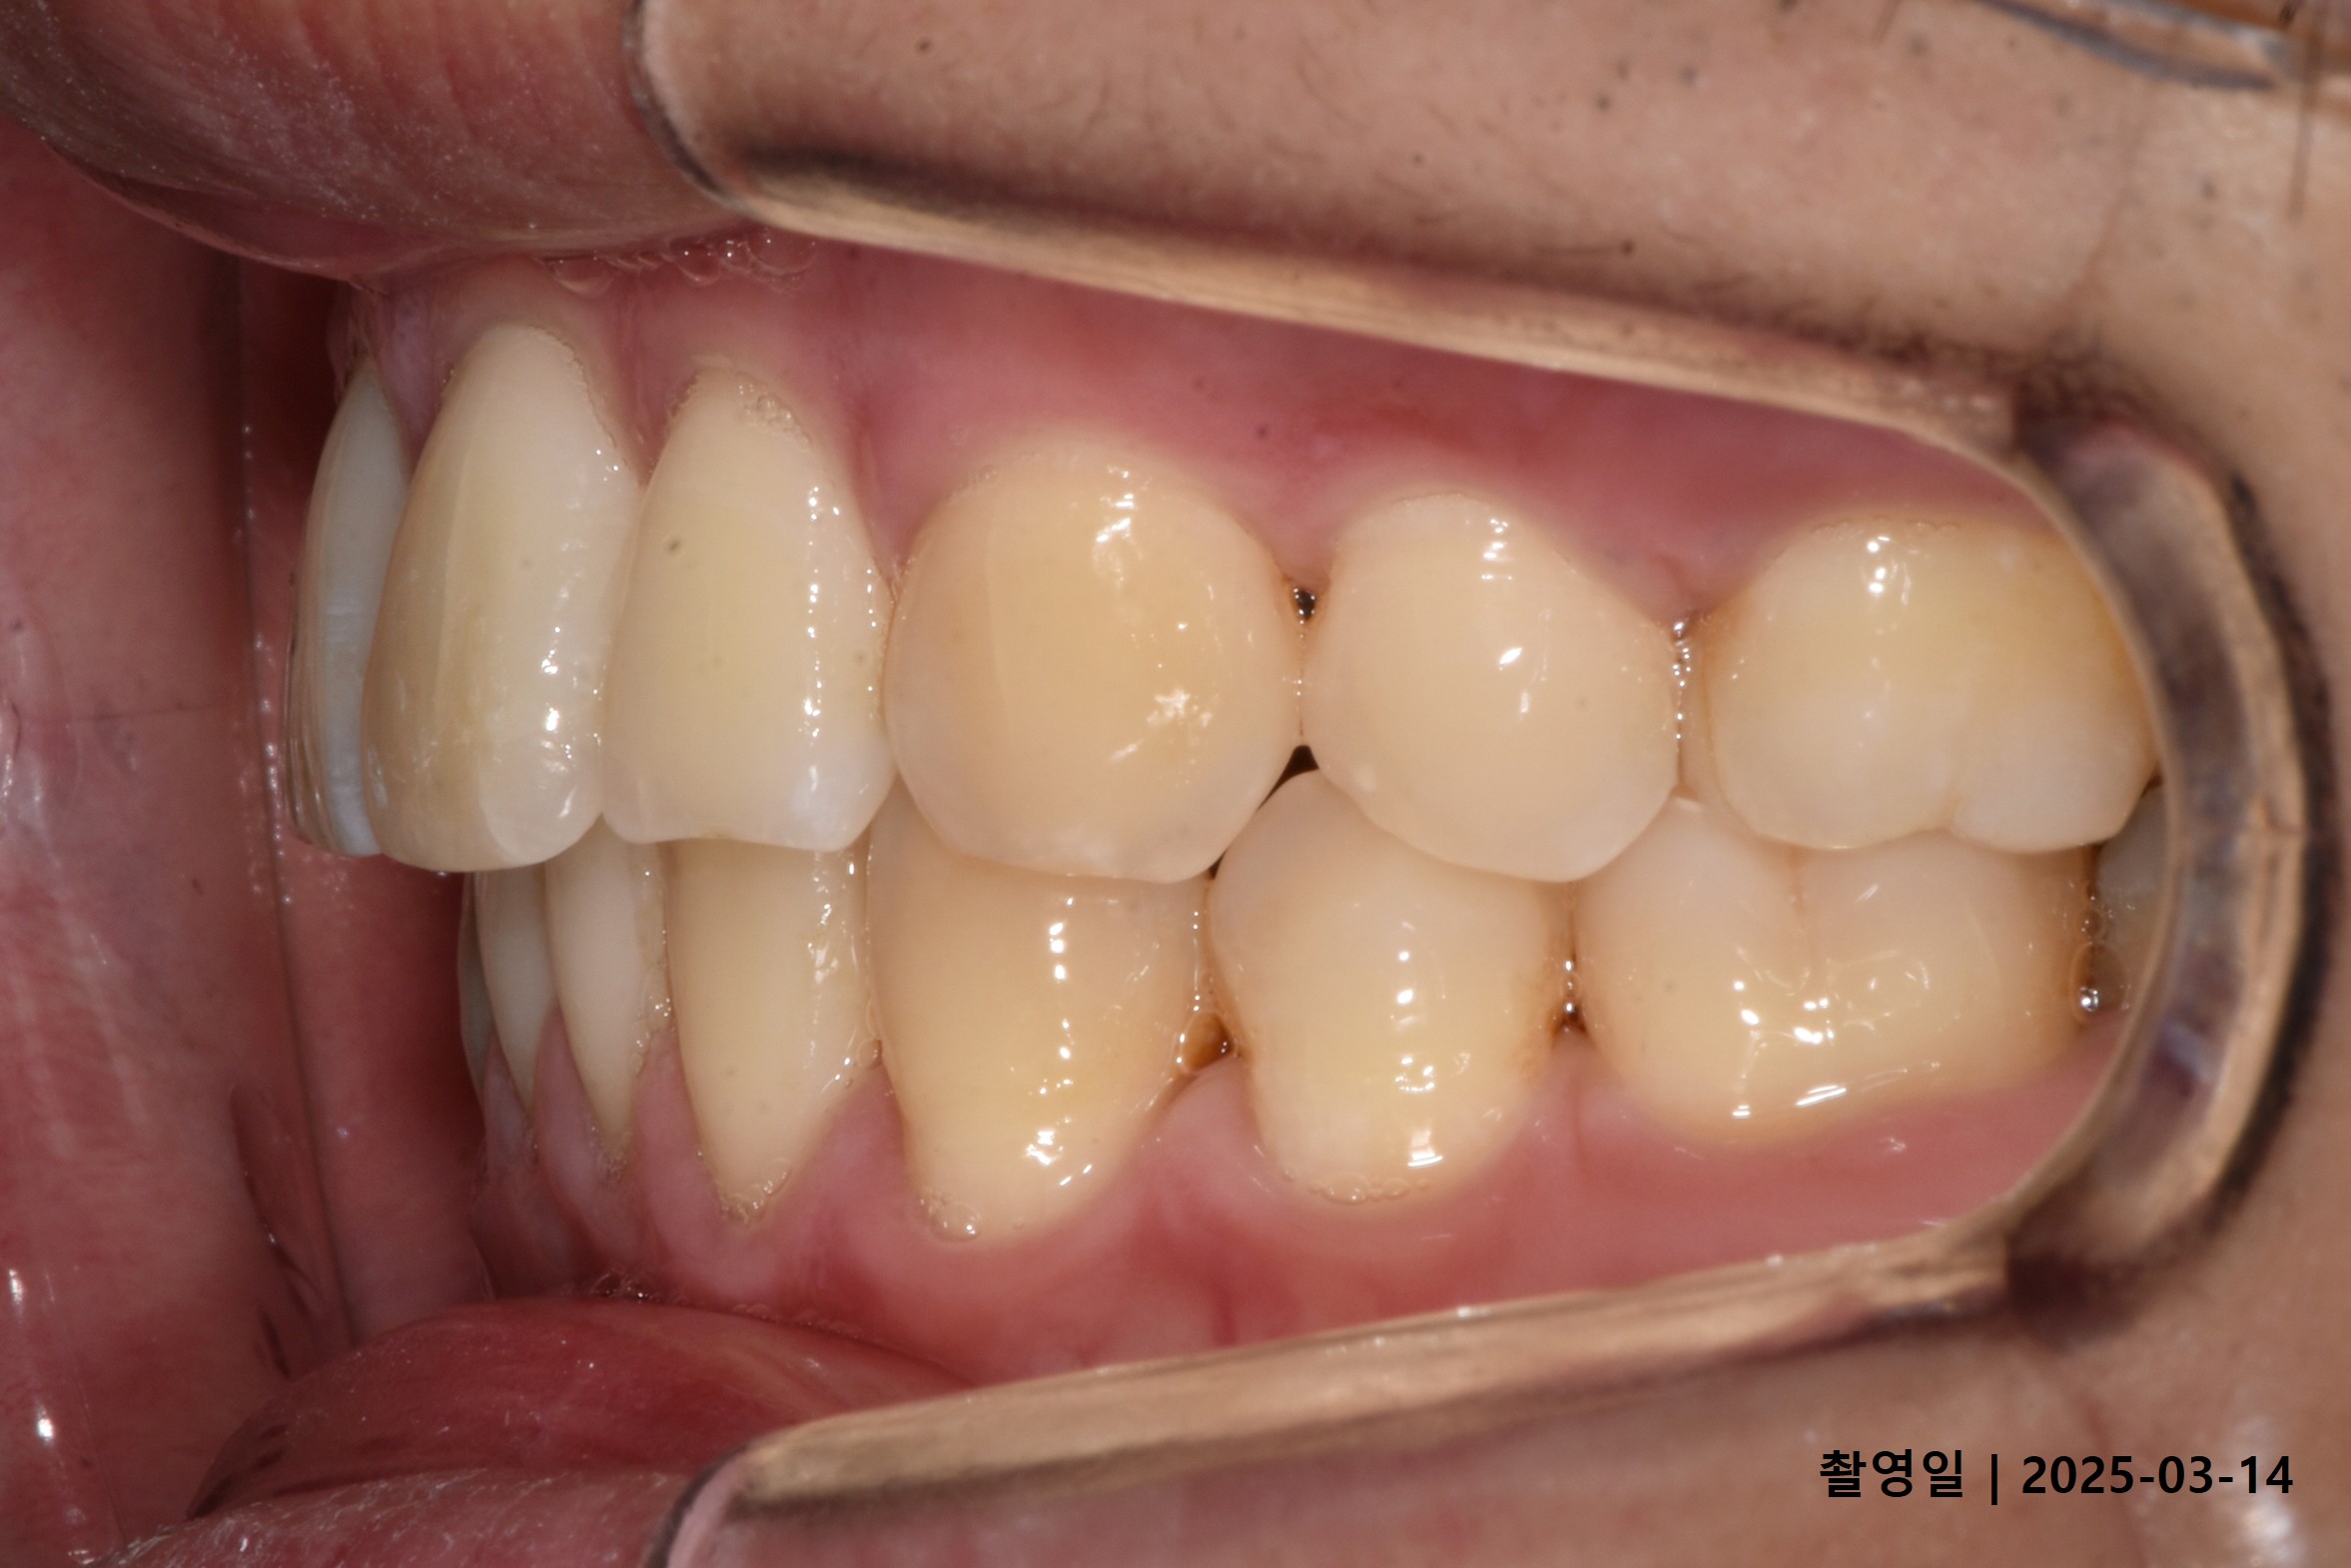

Case 2

- 24세 여성

- 상하악소구치 발치

- 치료기간 2년 1개월

치료 전

치료 후